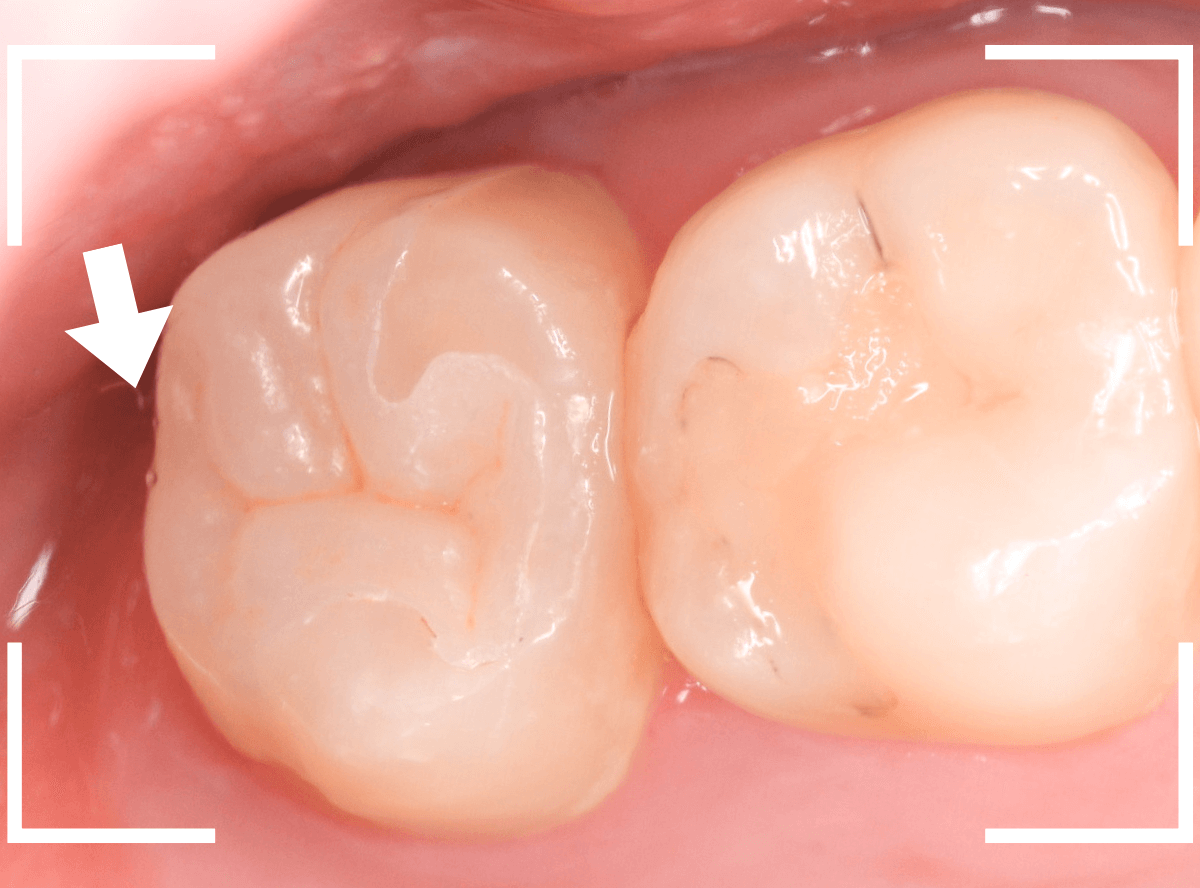

お口の中でsetしたところです。

ほとんど調整する事もなく、ピッタリと合わせる事ができました。

さて、こんな上の奥歯にセラミック系のつめものを入れるメリットはなんでしょうか。

お口を開けた時にも外からほとんど見えないと思います。

それは、清掃性だと私は思います。

矢印の部分、上の奥歯の奥側の部分は歯ブラシもなかなか届きません。

我々歯科医師が治療をする時もてこずる場所です、綺麗に磨けと言われてもなかなか難しいでしょう。

しかし、セラミック系のつめものは表面が非常につるつるしていますので、プラークがそこにとどまりづらいです。

磨けなくても大丈夫、とは言いませんが、金属などに比べてかなり虫歯になりづらく歯の長期保存には有利な素材です。

セラミック系の素材には見た目の美しさだけではなく、そういったメリットもある点を知っていただけますと幸いです。